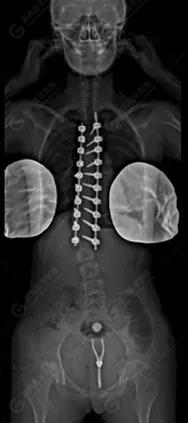

15歲女性,發(fā)現(xiàn)特發(fā)性脊柱側(cè)彎3年,于2019年1月23日來到廣東高尚醫(yī)學(xué)影像診斷中心行EOS檢查,2019年2月行手術(shù)治療后多次到中心行EOS復(fù)查。

2020-01-17

脊柱側(cè)彎最重要一個臨床參數(shù)是側(cè)彎角(Cobb角),目前臨床公認(rèn)的Cobb角>10 °診斷為脊柱側(cè)彎;如Cobb角進(jìn)行性持續(xù)性增加>40 °需要手術(shù)矯正治療。

本例患者胸椎右側(cè)彎,Cobb角(T6/T12)為47°,遂行手術(shù)矯正治療。術(shù)后多次隨訪的Cobb角(T10/L3)為12°-15°之間,較術(shù)前明顯縮小。

EOS在超低輻射劑量的情況下,保證高信噪比和高對比度的影像質(zhì)量。EOS 3D建模提供了精準(zhǔn)的自動臨床數(shù)據(jù)測量,避免了人工測量誤差,真正實現(xiàn)了骨放射領(lǐng)域的精準(zhǔn)治療、數(shù)字化建設(shè)與國際同步。術(shù)前計劃更加精準(zhǔn),術(shù)后評估從定性向定量轉(zhuǎn)變,更加客觀真實。EOS具有成像速度快、輻射劑量小、可模擬三維重建等優(yōu)點,尤其適合脊柱側(cè)彎患兒的篩查及定期隨訪。